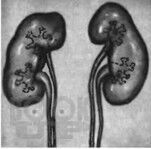

Пороки развития мочеполовой системы

Учебное пособие «Пороки развития мочеполовой системы» составлено в соответствии с программой по дисциплине «Патологическая анатомия, клиническая патологическая анатомия» для студентов по специальностям «Лечебное дело», «Педиатрия», «Медико-профилактическое дело». Учебное пособие может быть использовано во время практических занятий студентами лечебного, педиатрического и медико-профилактического факультетов.